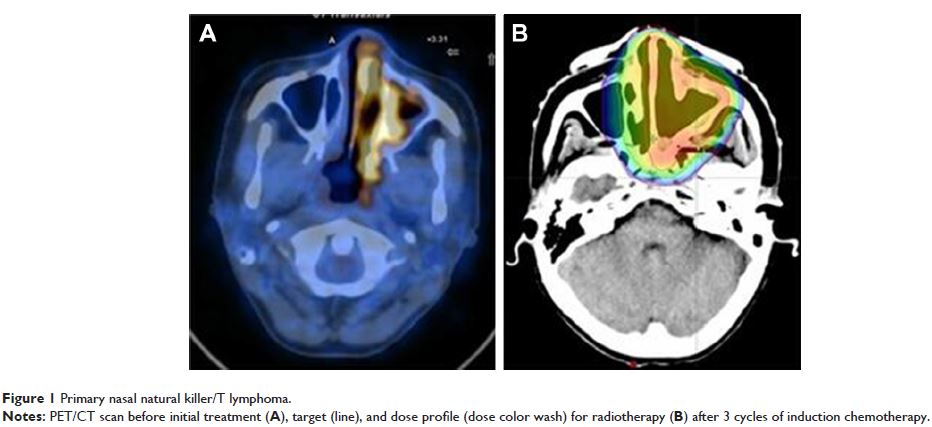

- 作者:Jiachen Luo, Liming Dai, Jianming Li, Jinlong Zhao, Zhiqiang Li, Xiaoming Qin, Hongqiang Li, Baoxin Liu, Yidong Wei

- 期刊:Clinical Interventions in Aging